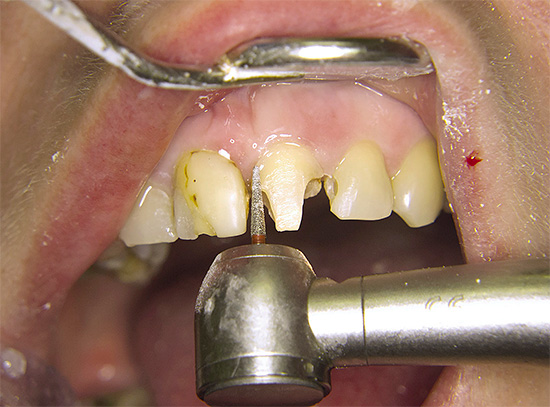

Per comprendere l'essenza del problema, il dentista chiarirà definitivamente la diagnosi, che è stata la prima terapia.Se è stato inserito un riempimento in caso di carie e il dente fa male a lungo ed è molto doloroso, il dentista esaminerà le otturazioni installate, la palpazione delle gengive, la percussione dei denti (toccando) e realizzerà un EDI per verificare la vitalità della polpa e la diagnostica a raggi X. Se viene confermata l'infiammazione del "nervo" o, peggio ancora, l'infiammazione alla radice, il medico condurrà estrazione di tutta la polpa dai canali e li sigilla per tutta la lunghezza.

Se un dente "morto" fa male dopo aver riempito i canali, il dentista farà sicuramente una radiografia. Se vengono rilevati errori nel trattamento, il dente verrà rianimato. In rari casi, se è impossibile trattare un dente, il medico suggerirà di rimuoverlo e al suo posto inserisce un impianto con una corona o crea un "ponte" con un dente artificiale.